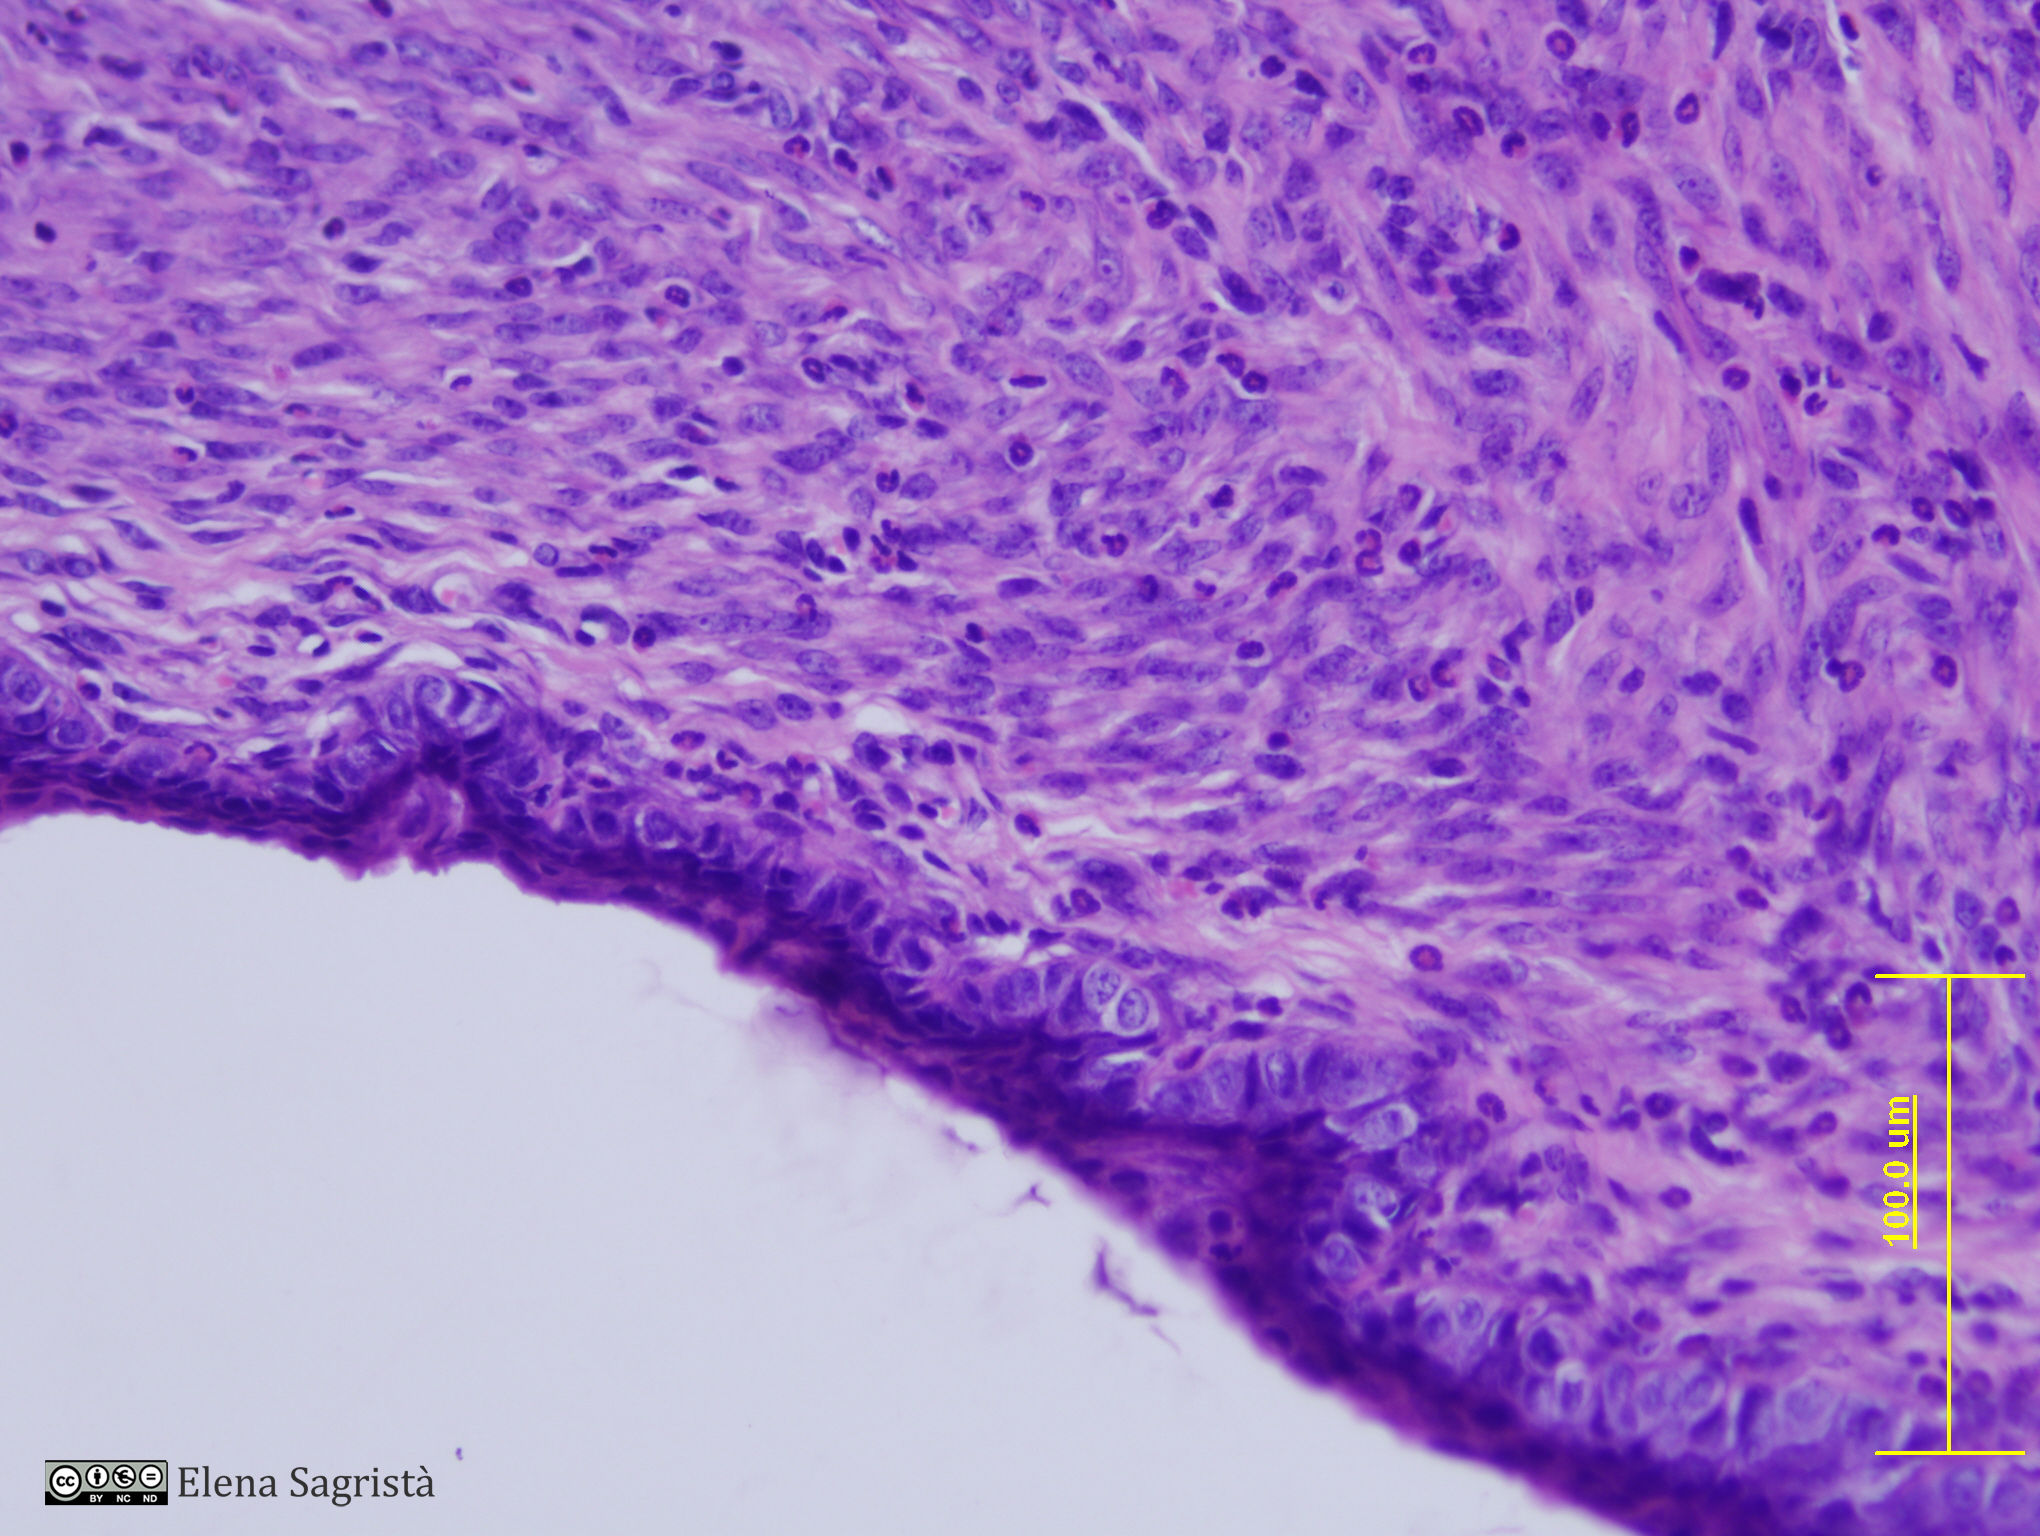

Imatges de preparacions histològiques d'Ovari i Aparell reproductor femení. Microscòpia òptica.